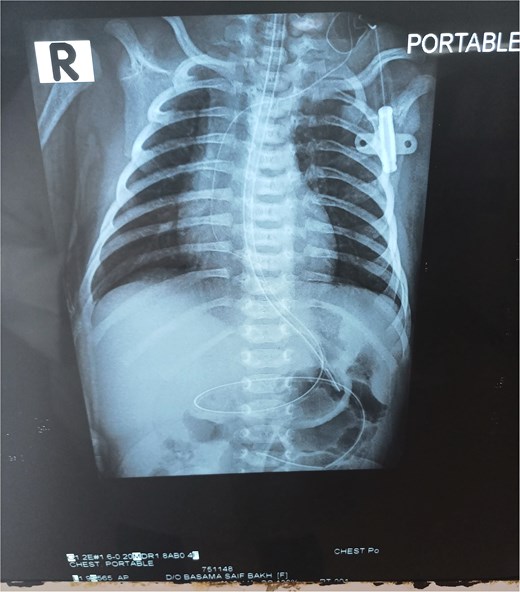

The patient had a naso-jejunal tube for feeding, instead of performing a feeding jejunostomy, and an orogastric tube for gastric decompression. The patient was left on nothing per oral until peristalsis was resumed. No drainage tubes were put for fear of infection. Vital signs were checked in the follow-up and an X-ray for chest and abdomen was done after 5 days (Fig. 4) then at 1 week post-operatively to exclude the formation of air under diaphragm. The post-operative period was uneventful, and the patient was discharged after 15 days from admission.